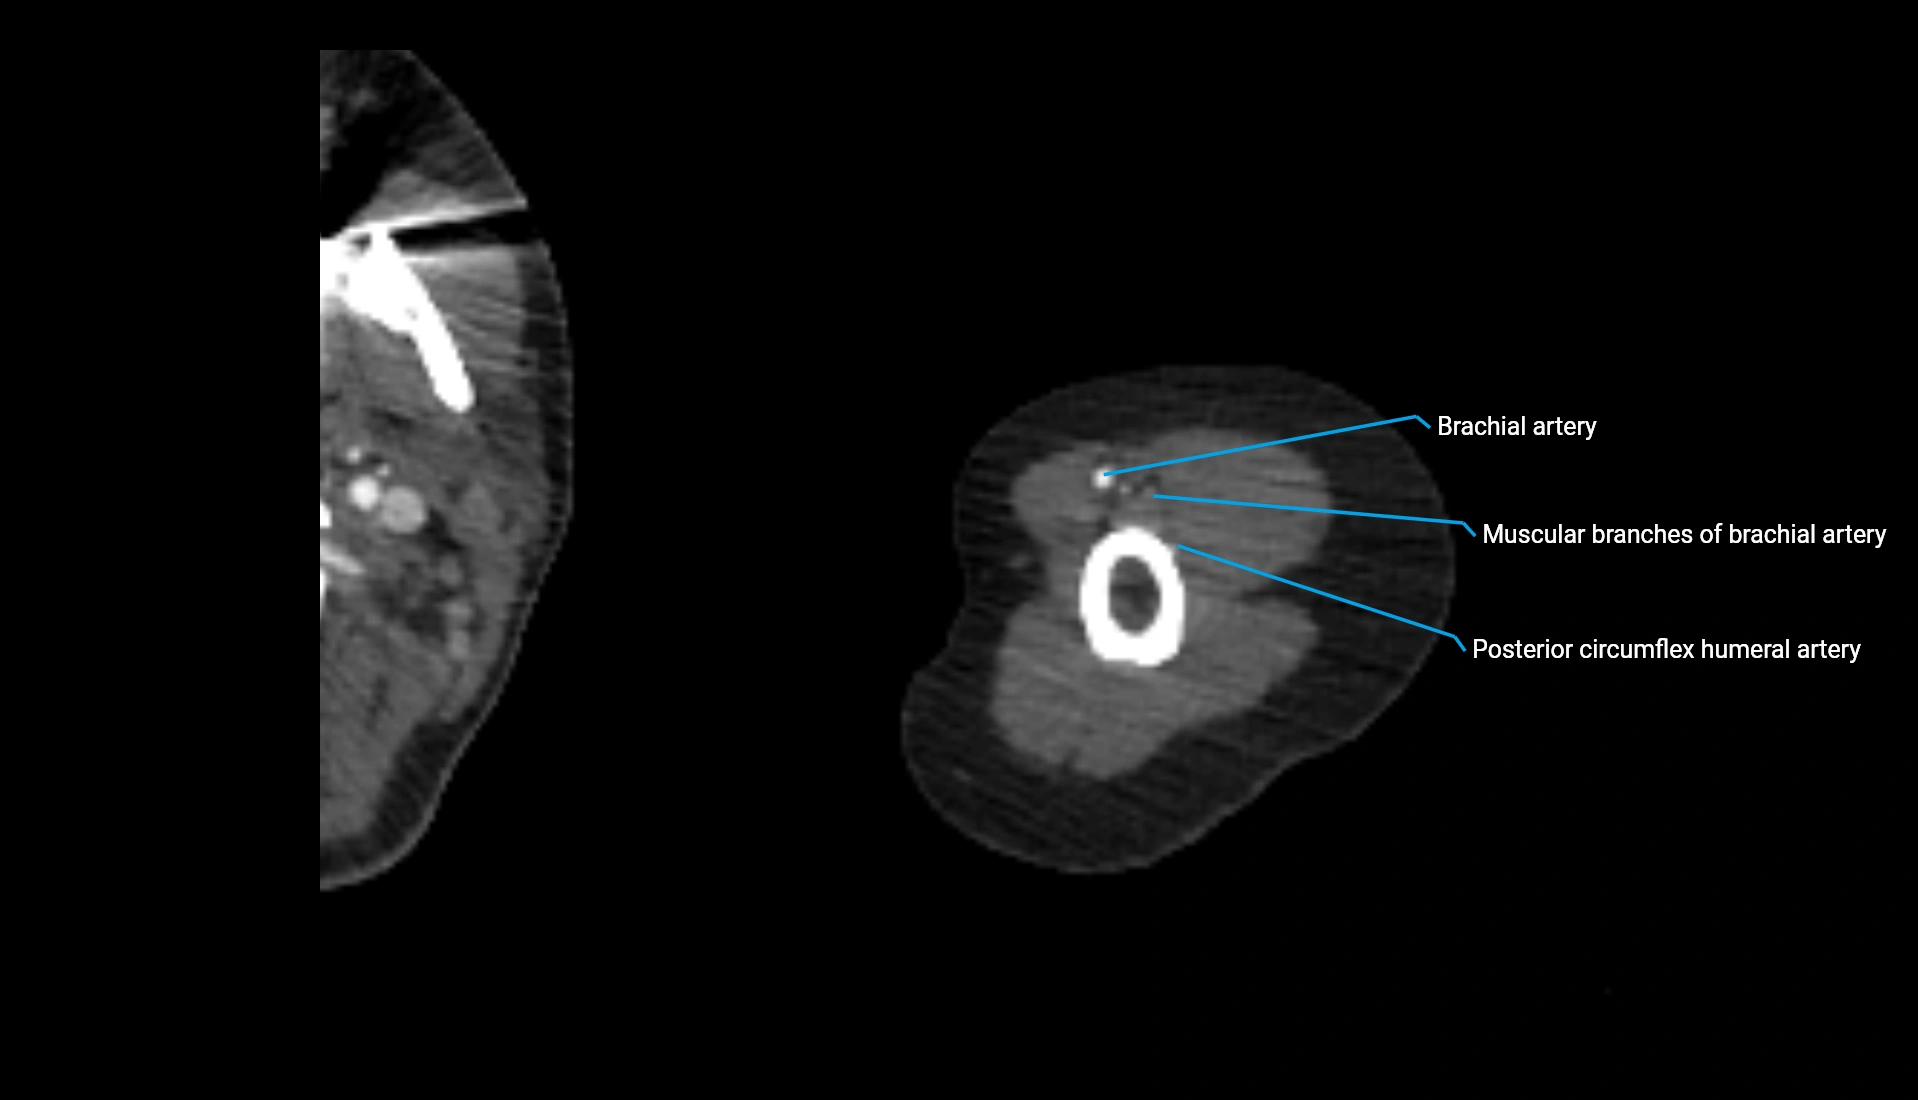

CT Appearance

Non-Contrast CT:

• Cortex: High-density, sharply defined

• Subchondral bone: Dense cancellous matrix

• Articular surface: Smooth concave contour articulating with the capitellum

• Excellent for evaluating bone integrity, alignment, and subtle fractures

Post-Contrast CT:

• Bone: No enhancement

• Joint capsule and synovium: Mild enhancement outlining the joint

• Improves contrast between soft tissues and bony margins

• Useful in detecting subtle joint abnormalities or postoperative changes